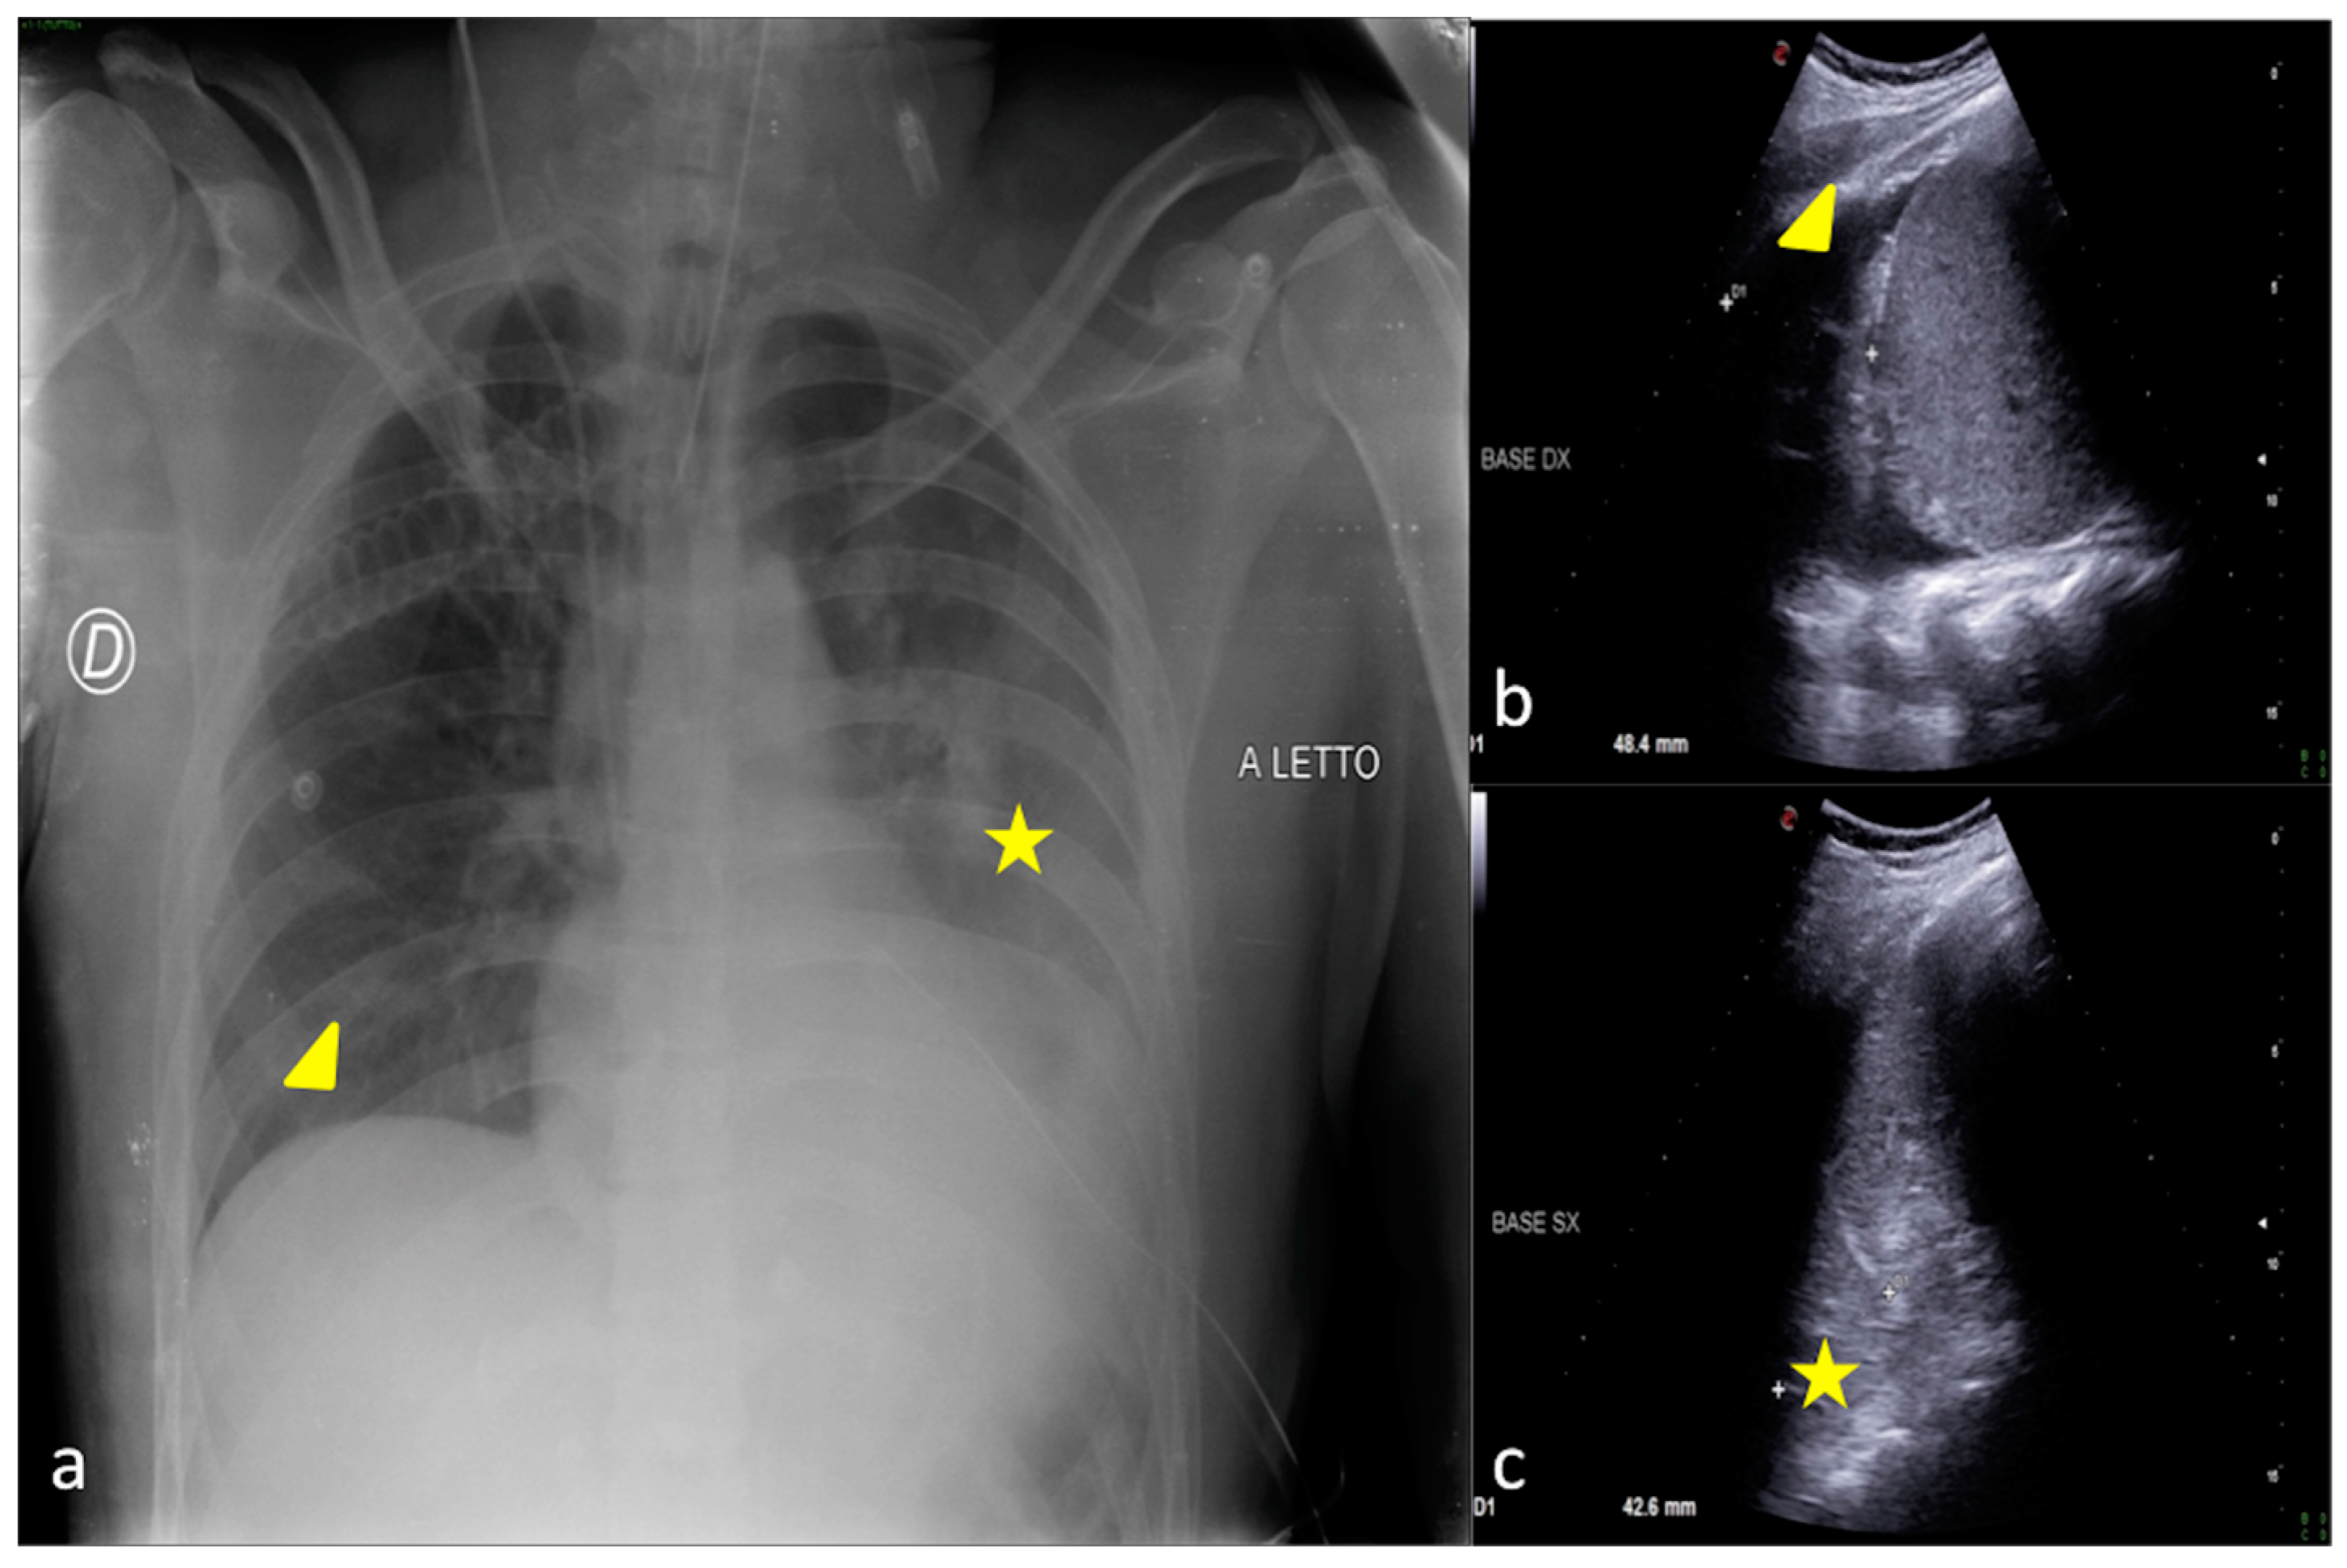

2.4. Cardiogenic Pulmonary Edema